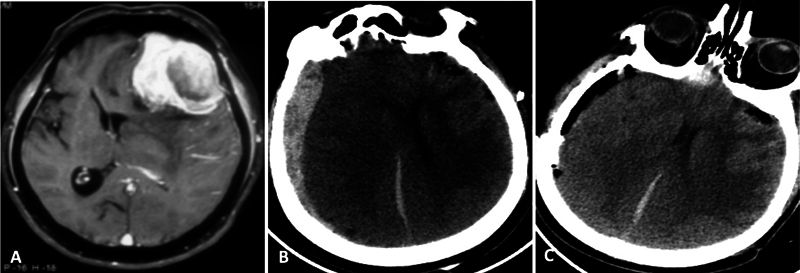

目的 颅内脑膜瘤占所有脑肿瘤的三分之一,是全世界神经外科手术最常见的适应症之一。大多数脑膜瘤症状不明显,病程较长。然而,有关脑膜瘤急诊手术结果的数据却很有限。本研究旨在介绍我们对急诊脑膜瘤患者进行紧急手术干预的经验。我们还分析了影响早期神经系统预后和并发症的因素。材料和方法 回顾性分析了 2015 年 1 月至 2019 年 12 月间所有非选择性急诊脑膜瘤手术。记录患者的人口统计学、临床和放射学细节,以便进行分析。手术过程、并发症和随访结果也包括在内,以便进行统计比较。结果 44 名患者符合研究条件,平均年龄(49.4±13.4)岁。患者的格拉斯哥昏迷量表(GCS)平均值为 13;47.7% 的病例出现感觉改变。最常见的病变位置是凸面(25 例,占 56.8%),平均肿瘤体积为 74.1 ± 36.5 mL。16例患者(36.4%)出现肿瘤周围水肿和肿块效应。随访 3 个月时的平均 Karnofsky 表情状态为 89.3 ± 18.2。患者年龄和肿瘤大小对预后没有影响。出现 GCS(P 0.03)和术后并发症(OR 25.71,CI 2.65-249.2,P 0.001)与不良预后有关。虽然没有统计学意义,但肿瘤分级较低也与较差的临床预后有关(P 0.20)。结论 脑膜瘤急诊手术的疗效和并发症发生率与常规择期手术相当。II/III 级脑膜瘤更有可能出现急性神经功能恶化,预后相对较差。在我们的研究中,GCS表现不佳和术后并发症是导致患者预后不佳的最关键因素。

Objective  Intracranial meningiomas constitute a third of all brain tumors and are among the most common indications for neurosurgical procedures performed worldwide. Most meningiomas present with an indolent, longstanding history. However, the data on outcomes of emergency surgeries for meningioma is limited. This study aims to present our experience of urgent surgical intervention in patients with meningiomas presenting acutely. We also analyze the factors influencing early neurological outcomes and complications. Materials and Methods  All nonelective meningioma surgeries done on an emergency basis between January 2015 and December 2019 were retrospectively reviewed. Patients' demography, clinical, and radiological details were recorded for analysis. The surgical procedure, complications, and follow-up outcomes were also included for statistical comparison. Results  Forty-four patients qualified for the study with a mean age of 49.4 ± 13.4 years. The average presenting Glasgow Coma Scale (GCS) was 13; 47.7% of cases presented with altered sensorium. The most common lesion location was convexity (25, 56.8%), and the mean tumor volume was 74.1 ± 36.5 mL. Gross peritumor edema with mass effect was seen in 16 patients (36.4%). The mean Karnofsky Performance Status at 3 months' follow-up was 89.3 ± 18.2. Patient age and tumor size did not affect outcomes. The presenting GCS of < 15 (odds ratio [OR] 8.8, confidence interval [CI] 0.95-80.72, p 0.03) and the occurrence of postoperative complications (OR 25.71, CI 2.65-249.2, p 0.001) were associated with unfavorable outcomes. Although not statistically significant, a poor tumor grade was also associated with worse clinical outcomes ( p 0.20). Conclusion  Emergency meningioma surgery has comparable outcomes and complication rates with routine elective procedures. Grade II/III meningiomas are more likely to present with acute neurological deterioration and carry a relatively worse prognosis. Poor presenting GCS and postoperative complications are the most critical factors associated with poor patient outcomes in our study.